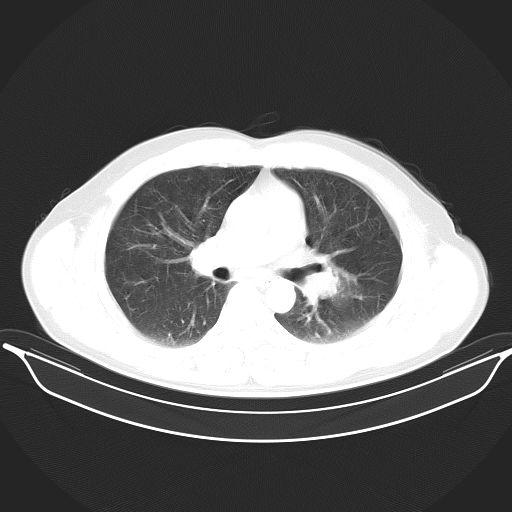

标题: CT25490:男,40岁,体检发现;无其它不适。 [打印本页]

标题: CT25490:男,40岁,体检发现;无其它不适。

考虑:1、过各敏性肺炎可能性大,建议定期复查。

多考虑结核。

考虑肺霉菌病。

转移性肺肿瘤不排除,建议结合相关检查考虑

考虑右下肺周围性肺癌并肺内多发转移,纵隔淋巴结转移!